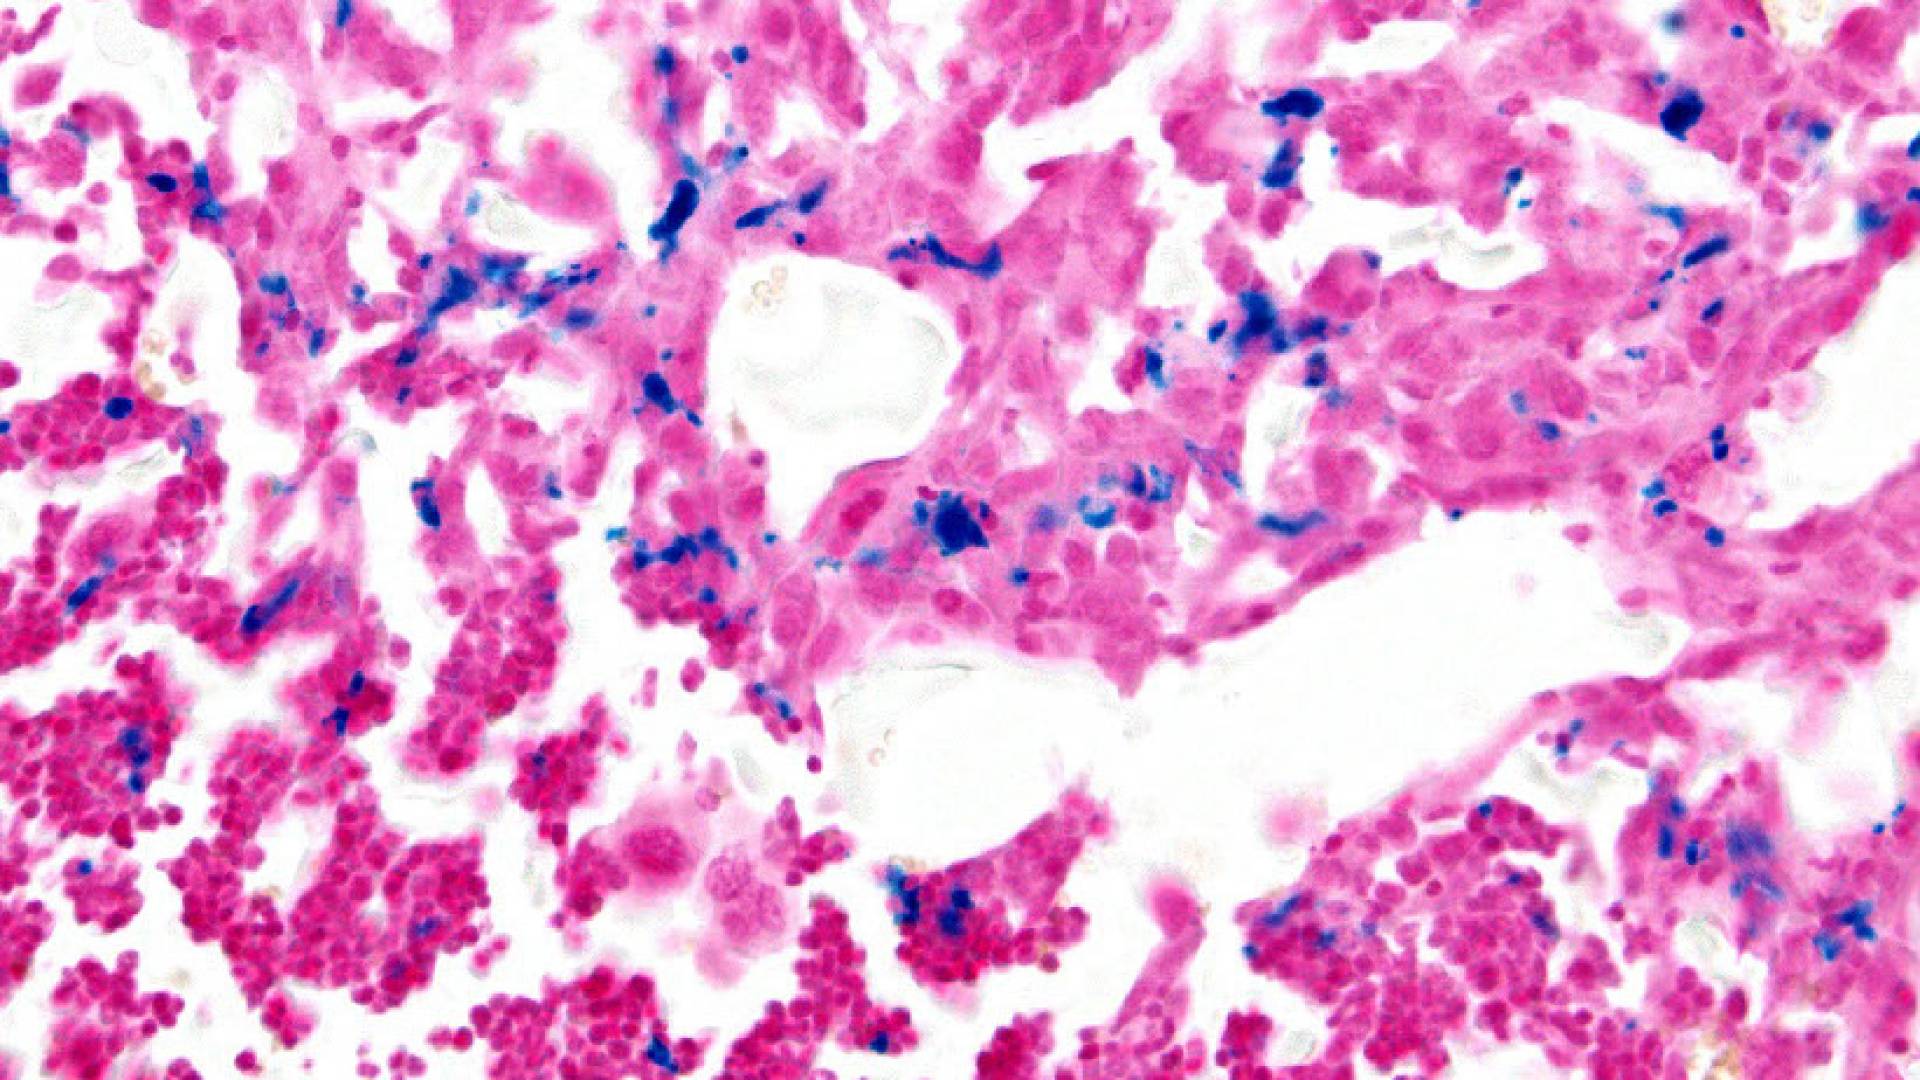

To start extending their results to humans, the geoscientists obtained some cancerous and healthy mouse liver cells from then-graduate student Zhaoyue Zhang (a 2021 Ph.D. alumna) in the Rabinowitz lab, now a postdoc at the Rockefeller Institute. Like in yeast, the D to H ratio in fermenting cancer cells was lower than in healthy, respiring cells.